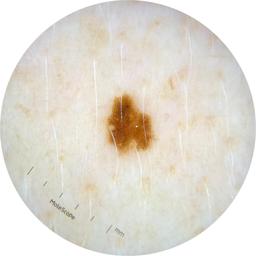

ISIC_2261268

acquisition_day 307

age_approx 50

anatom_site_1 Trunk

anatom_site_2 Posterior trunk

anatom_site_general posterior torso

diagnosis_1 Benign

diagnosis_confirm_type single image expert consensus

image_type dermoscopic